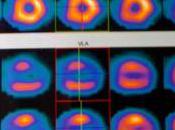

A propos de ma santé....

Quelques nouvelles, pour celles - notamment au loin - que le sujet intéresse.J'ai vu mon cardiologue, qui est content des résultats du test d'effort. Lire la suite

Le 06 avril 2011 par Mpbernet